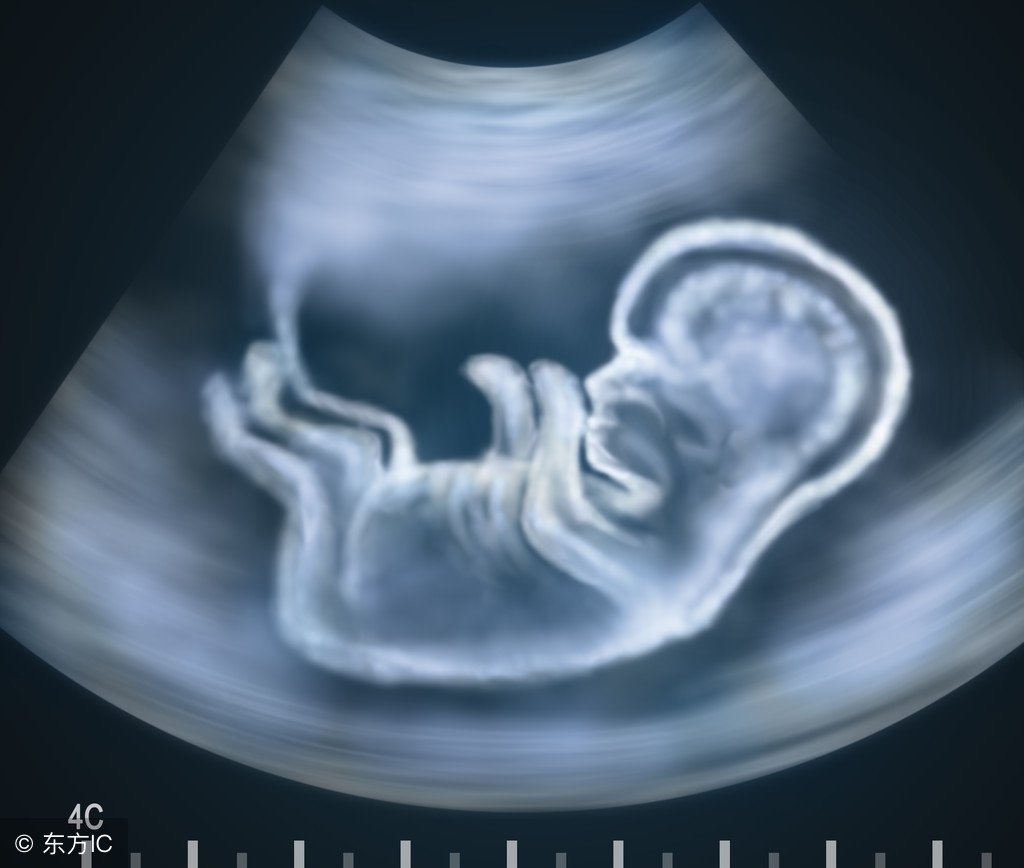

如果你记不清楚自己末次月经的日子,或者月经不规律,那么通过B超方式可以得知孕周,B超中医生会通过胎儿双顶径、头臀长度、股骨长度等数据估算出胎儿的月份。